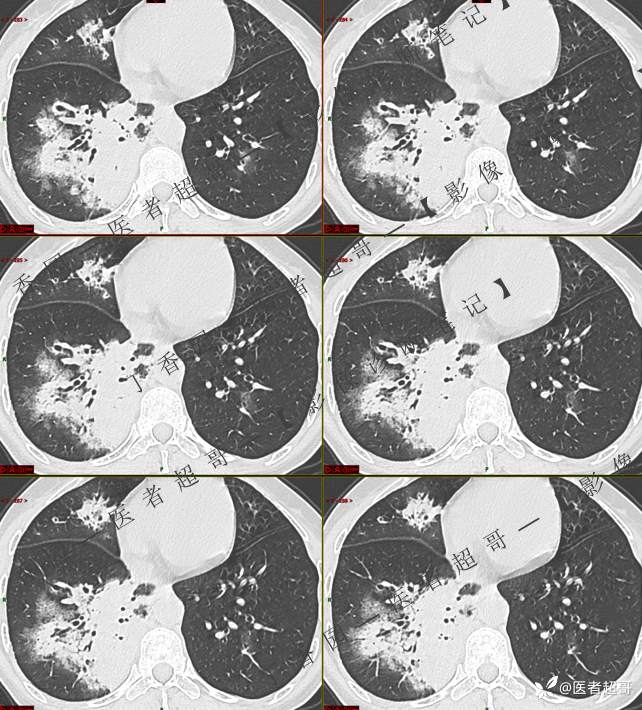

临床治疗一周后复查